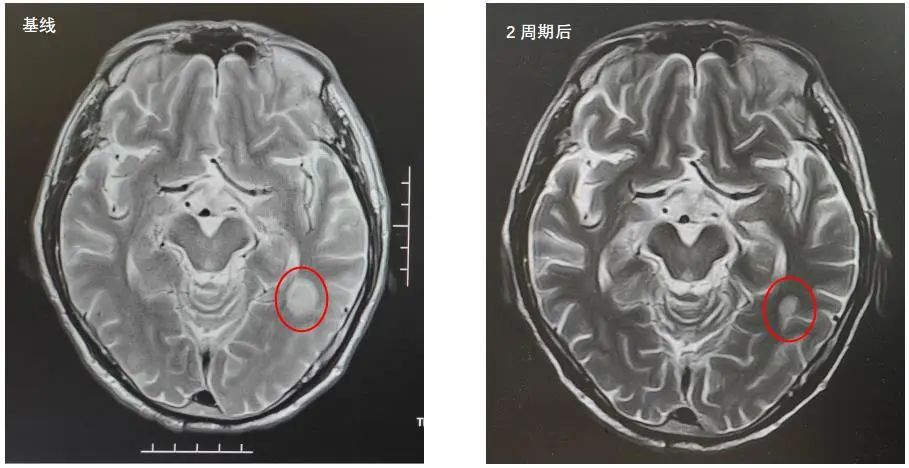

2022年5月9日MRI结果:左侧颞叶强化灶,考虑转移瘤。

2022年7月5日复查脑部MRI提示:与PACS20220529老片对比,现片示:左侧颞叶强化灶较前稍缩小。

MRI:与PACS20220529老片对比,现片示:左侧颞叶强化灶较前稍缩小。

该患者是一个基线伴有脑转移的广泛期小细胞肺癌患者,《2022年CSCO小细胞肺癌诊疗指南》推荐,对于无症状的脑转移小细胞肺癌患者,一线治疗推荐免疫联合化疗后,再行全脑放疗。此患者在进行4个周期斯鲁利单抗联合卡铂依托泊苷治疗后,影像学提示病灶明显退缩,脑转移病灶也明显缩小,疗效达到PR,充分证明斯鲁利单抗在广泛期小细胞肺癌患者中的良好疗效。